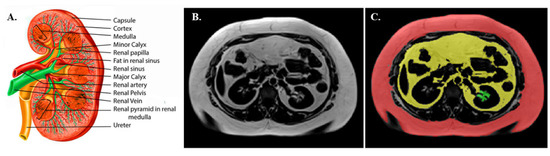

3.4. Renal Sinus Fat Area (RSF) Determination